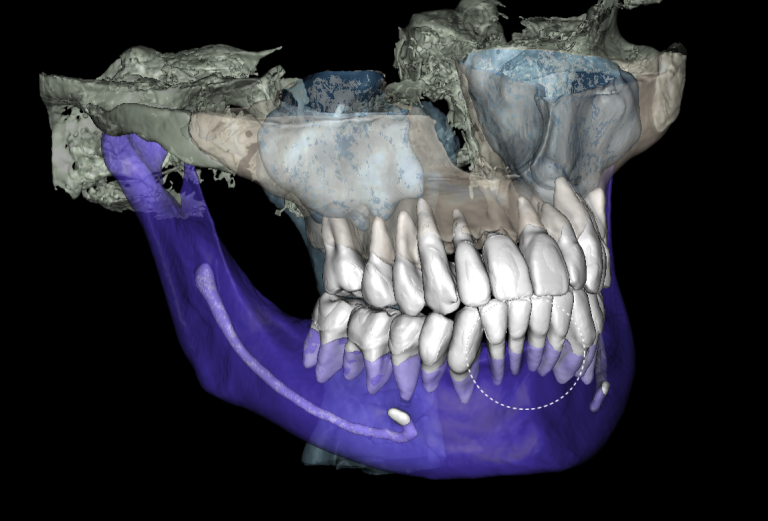

Solution: The automated process of segmentation and formation of 3D models from DICOM files allows extracting individual structures for subsequent 3D printing. The printed model of the third molar, taken from the “STL” module of Diagnocat, is used to prepare the socket for the transplanted tooth. The 3D reconstruction generated using Diagnocat displays the structure of the jaws and teeth and enables the visualization of tooth 37 (Universal 18) with periapical lesion around the roots. In this case, Diagnocat serves as a communication tool that helps convince the patient of the importance of timely implementation of the proposed treatment plan.